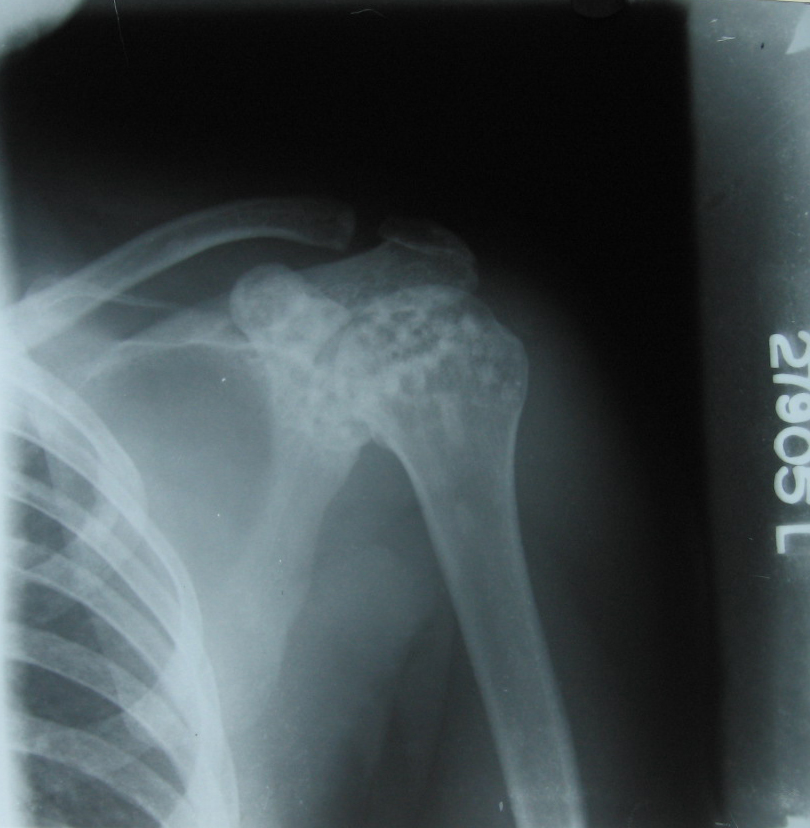

FIG.2